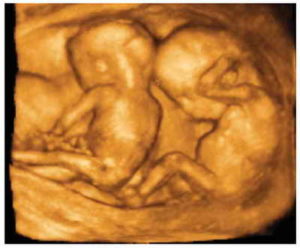

В первую очередь диагност определяет количество плодов в маточной полости и их предлежание. Если младенец занимает поперечное либо тазовое положение, на данном сроке это не является патологией.

- одно- и многоплодной;

Эти предположения могут возникать как по данным других исследований (перинатальный скрининг), так и патологии у близких родственников. Кроме того, трехмерное сканирование стоит сделать женщинам с отягощенным акушерско-гинекологическим анамнезом, пациенткам после ЭКО, ИКСИ, MESA и при многоплодной беременности.

- при многоплодной беременности только 3Д-УЗИ способно предоставить достоверную информацию о развитии детей;